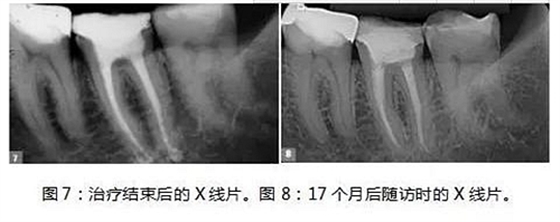

制備MTA-FILLAPEX糊劑并用主牙膠將其導(dǎo)入到根管內(nèi)(圖6)。使用攜熱器(Touch’n Heat, Kerr))除去過量的糊劑,熱垂直加壓。髓室用光固化復(fù)合樹脂密封,病人回到她的牙科醫(yī)生處,完成最終修復(fù)體的制作(圖7)。

17個(gè)月后,患者回訪, X線片結(jié)果顯示治療效果相當(dāng)成功(圖8),患者沒有陽性的癥狀和體征,牙齒的生理功能正常,根尖位置正常,根尖周多余的MTA-FILLAPEX已經(jīng)吸收干凈了。